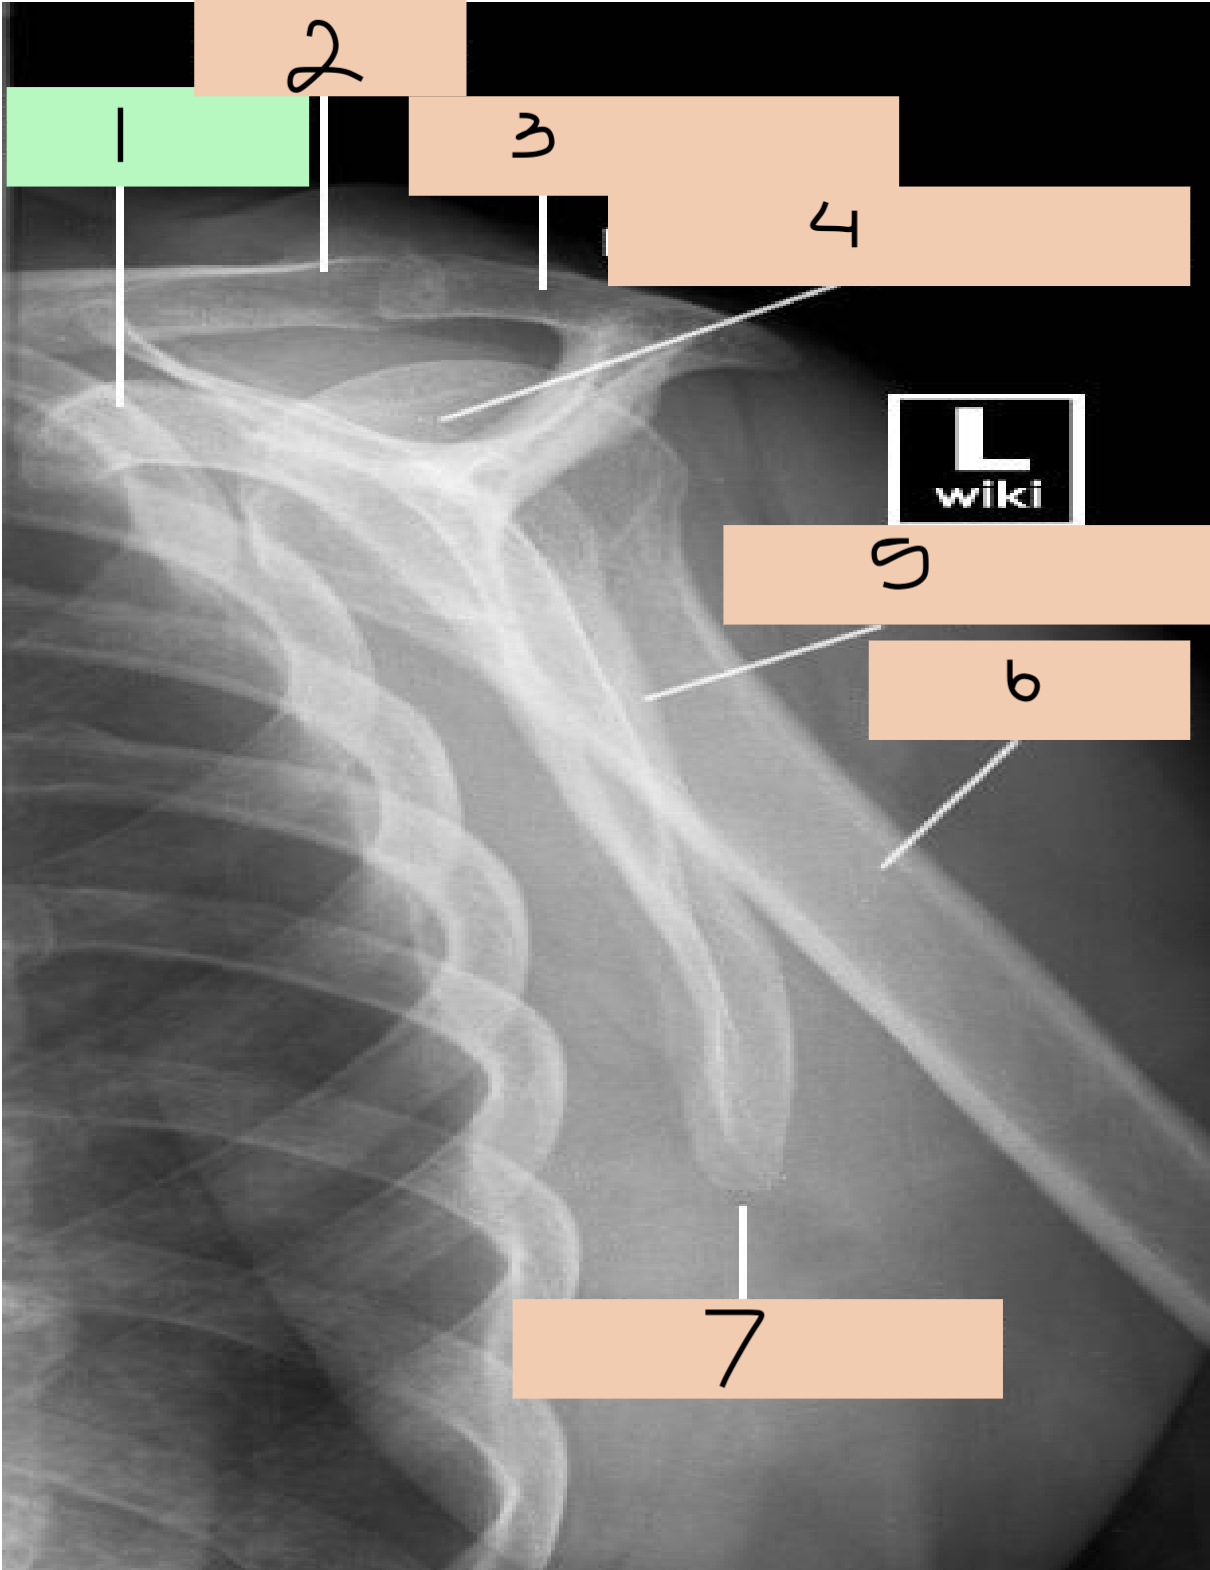

1

acromium process

2

head humerus

3

greater tuberosity

4

surgical neck

5

lesser tuberosity

6

supraglenoid tubercle

7

coracoid process

8

glenoid cavity

9

anatomical neck

10

infraglenoid tubercle

11

lateral border scapula

12

medial border scapula

13

inferior angle of scapula

14

scapula

15

clavicle